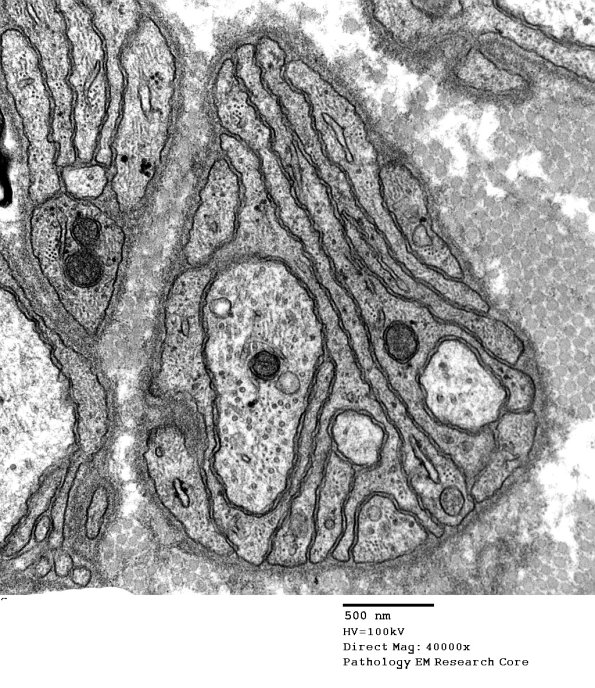

Here, it is clear that only a few axons are part of this band of Büngner.